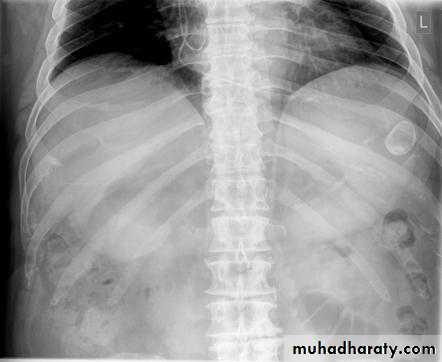

Dilatation of the bowel

Dilatation of the bowel is the cardinal plain film sign of intestinal obstruction

If the bowel is dilated it is important to try and decide which portion is involved

The valvulae conniventes (seen in proximal and mid small bowel) are always closer together than the colonic haustra and cross the width of the bowel , often giving "stack of coins" appearance

The colonic haustra ,which usually form incomplete bands across the colonic gas shadows, are always present in the ascending and transverse colon, but may be absent distal to the splenic flexure

Small bowel obstruction

Large bowel obstruction

Valvulae conniventes

Present

Absent

Number of loops

Many

Few

Distribution of loops

Central

Peripheral

Haustra

Diameter

3 – 5 cm

More than 5 cm

Radius of curvature

Small

Large

Fecal material